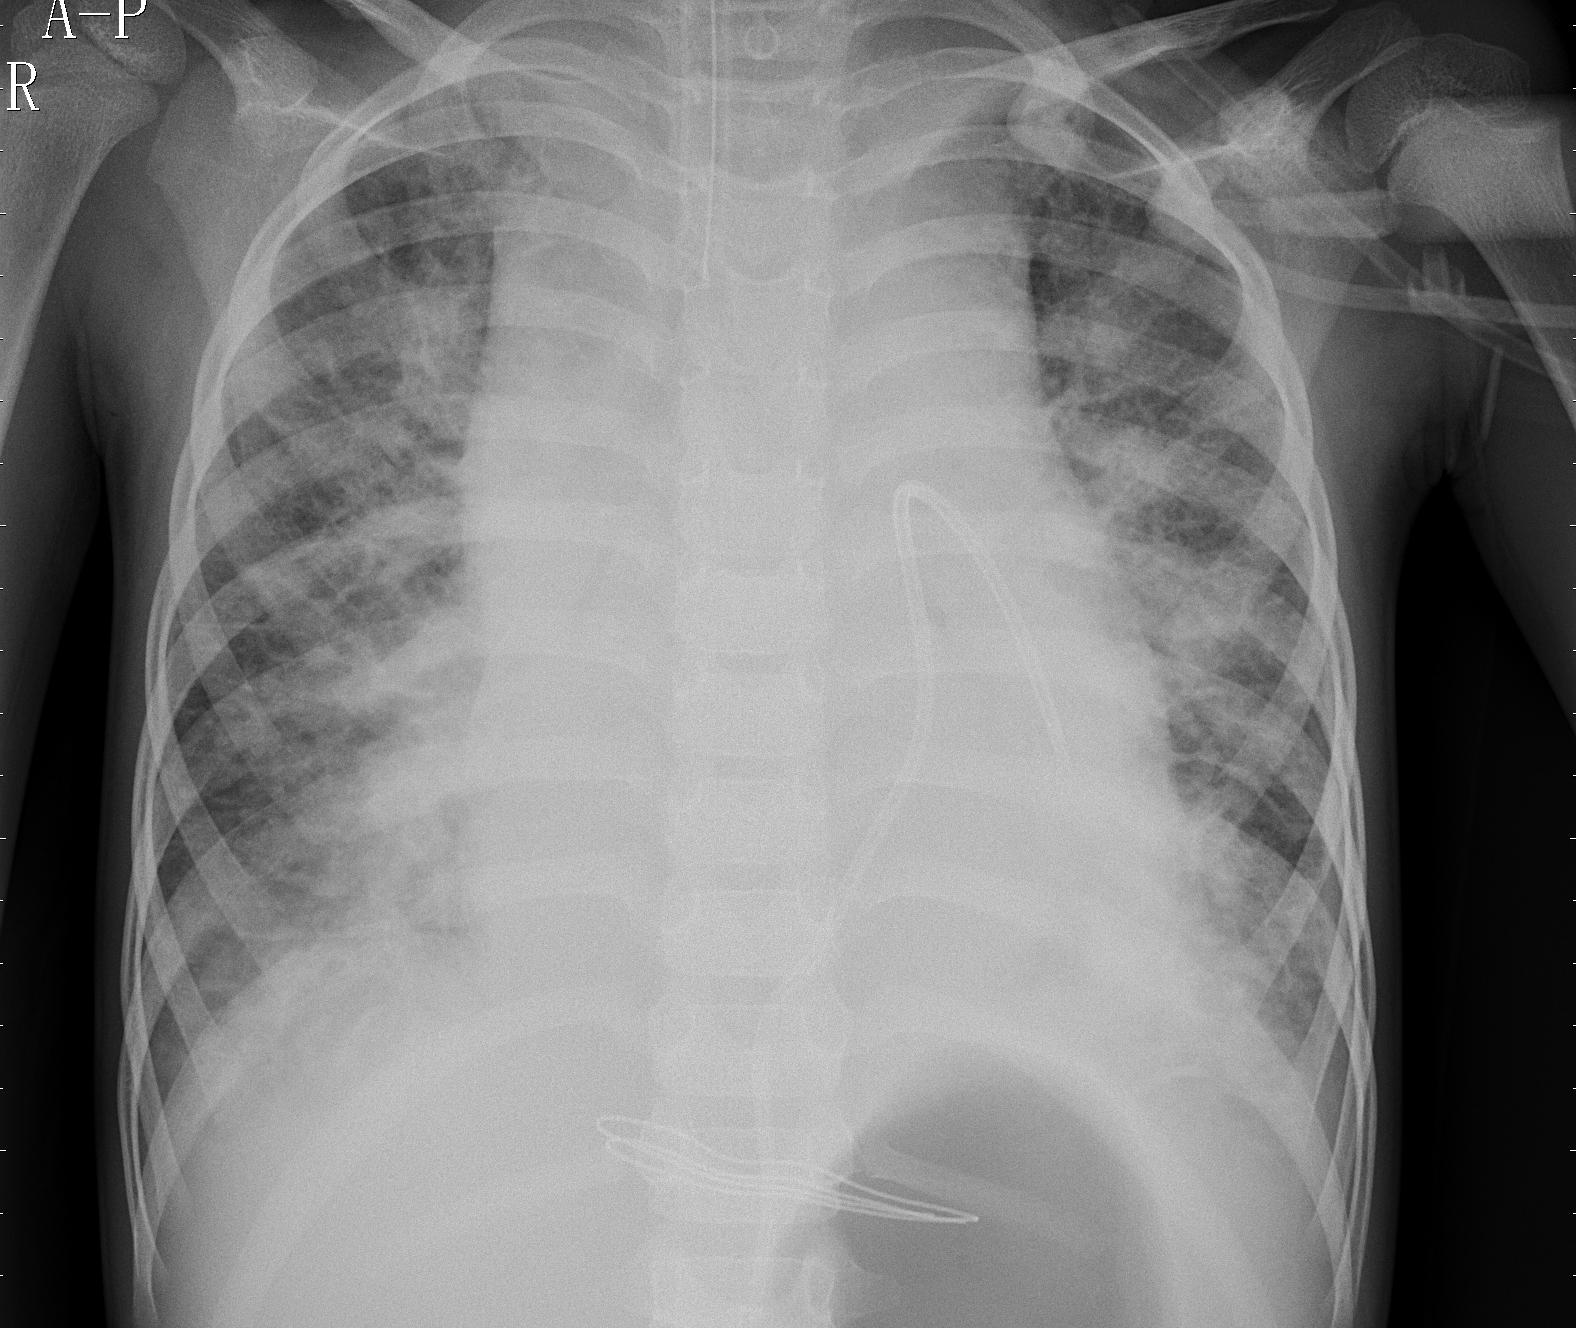

Refer to caption

(a) silicosis

(b) normal

(c) bacterial

(d) viral

Figure 2: Sample images corresponding to four classification categories.

Alongside the aforementioned dataset, we additionally incorporate data from [35]. Within the three classes of this dataset, we utilize 2772 images from the bacterial class and 1493 images from the viral class. These two categories correspond to distinct disease-causing agents, which are bacteria and viruses. The inclusion of these two classes in the overall dataset for the classification model aids the system in distinguishing between different types of pneumonia and their respective causative agents. The illustration in Figure 2 depicts examples of images corresponding to each category within the SVBCX dataset. This discrimination enables the system to make informed decisions for subsequent actions in patient care.